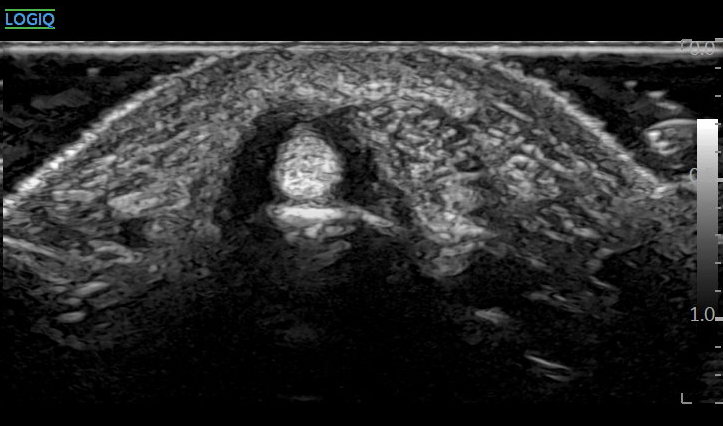

@ 바로한의원 열결혈 초음파

바로 이 '열결혈' 부위에서

두 개의 힘줄(APL, EPB)을 각각 구별하고,

힘줄 사이에 칸막이가 있는지 확인하고요.

어느 쪽 힘줄과 터널이 얼마나 부어있는지

정상측과 비교합니다.

'표준 경혈 초음파 영상'과 비교했을 때

차이가 보이시나요?